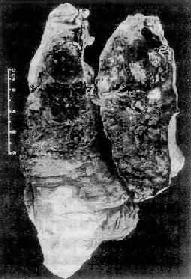

图9-24 Ⅲ期矽肺并发肺心病

两肺坚实能竖立,胸膜增厚。右心显著肥大、扩大,心尖由右心构成